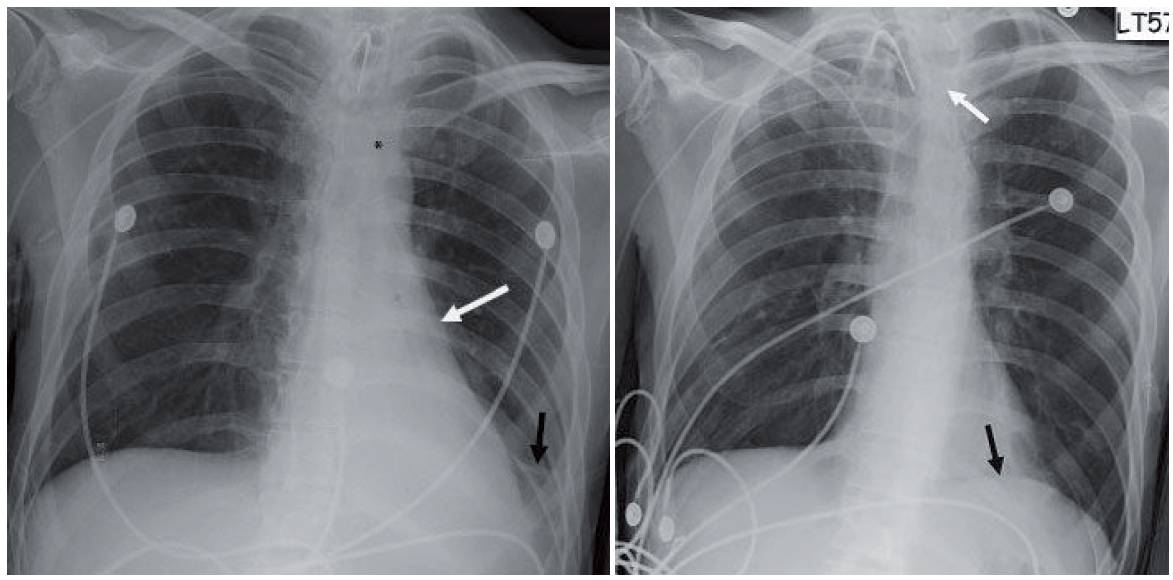

- Initial chest radiograph (first image) shows a retrocardiac opacity with air bronchograms and narrowed distances between the left ribs. The left hemidiaphragm cannot be seen behind the heart and the left heart border appears straightened. Also note the inferior location of the left hilum.

- Follow-up chest radiograph obtained the following day shows near-complete resolution. The left hemidiaphragm can now be seen (black arrow in second image) and the left heart border has regained the normal curvature. The peripherally inserted catheter flipped into the left brachiocephalic vein (white arrow).

- The altered left heart border appears straighter than normal. This finding has been referred to as the flat waist sign (white arrow in first image).

- Lingular linear atelectasis is another finding in left lower lobe collapse (Nordentsrom’s sign). This comes from the altered orientation of the lingular bronchi with hyperexpansion (black arrow in first image).

- Two other findings of left lower lobe collapse include shift of the anterior junction line and the top of the knob sign. In the latter, shifted mediastinal soft tissues obscure the top of the aortic arch (asterisk in first image).